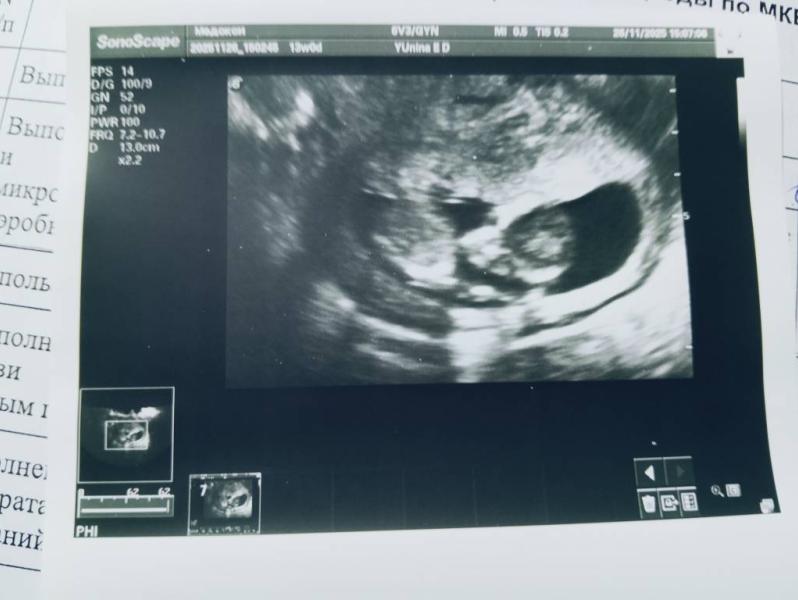

Были сегодня с мужем на узи (1 скрининг ), всё хорошо , соответствуем сроку 13 недель ☺️пдр 3.06.2026, узнали что ждем девочку🌸